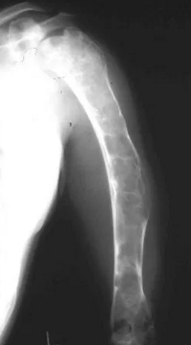

A quel âge peut-on avoir un Fibrous Xanthomas congénital ? Passé cet âge, comment cela s’appelle-t-il ?

On peut avoir un Fibrous Xanthomas congénital entre 4 et 8 ans.

Après 8 ans, cela s’appelle un fibrome non ossifié. (Non-ossifying fibroma)

A partir de combien de cm un Fibrous Xanthomas peut faire risquer une fracture ?

8 cm

S’il y a plus de 3 tâches de Fibrous Xanthomas, spécialement au niveau du genou, que peut-on craindre ?

Une neurofibromatose (pustule café au lait sur la peau) associée à la maladie : Von Recklinhausen’s disease